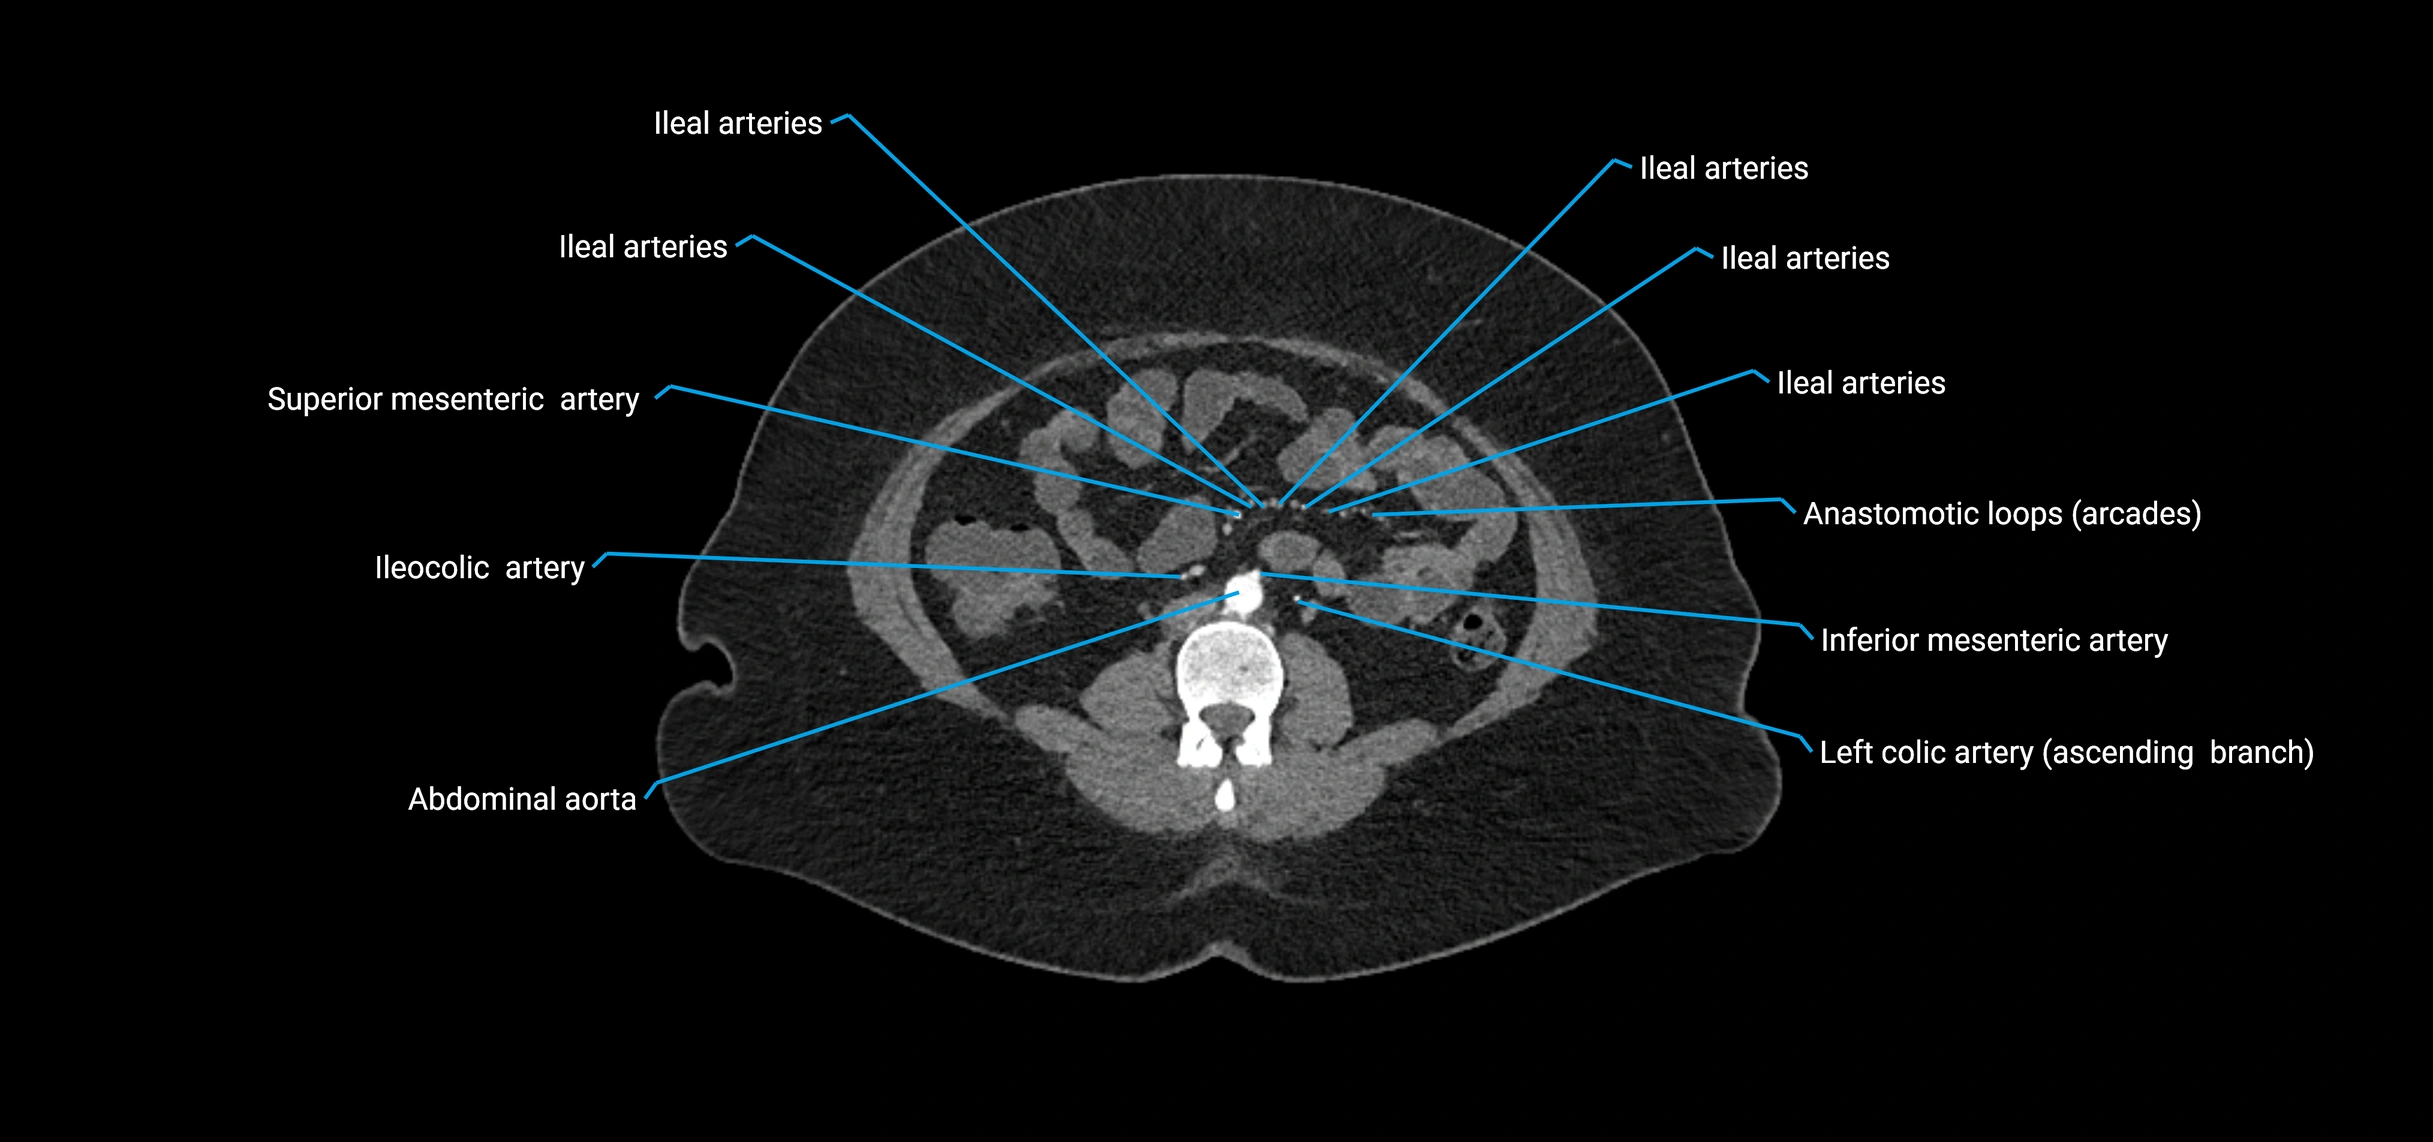

CT images

image

Contrast-enhanced CT (CTA):

• Gold standard for abdominal aortic imaging

• Provides excellent detail of lumen, wall, aneurysm, thrombus, and branch vessels

• Multiplanar and 3D reconstructions help in aneurysm measurement, stent graft planning, and dissection evaluation